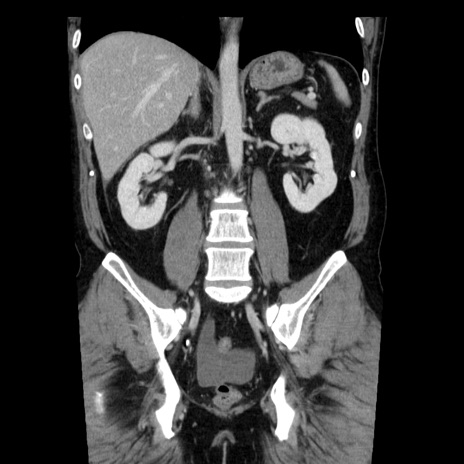

症例29(冠状断像)

【症例】40歳代男性

【現病歴】2日前から胃痛あり。徐々に周期的な激痛に変化した。本日になっても激痛があるため受診。

【身体所見】意識清明、BT 38-39℃台あり、腹部:膨満、やや硬、右下腹部に圧痛あり。

【データ】WBC 8500、CRP 23.26